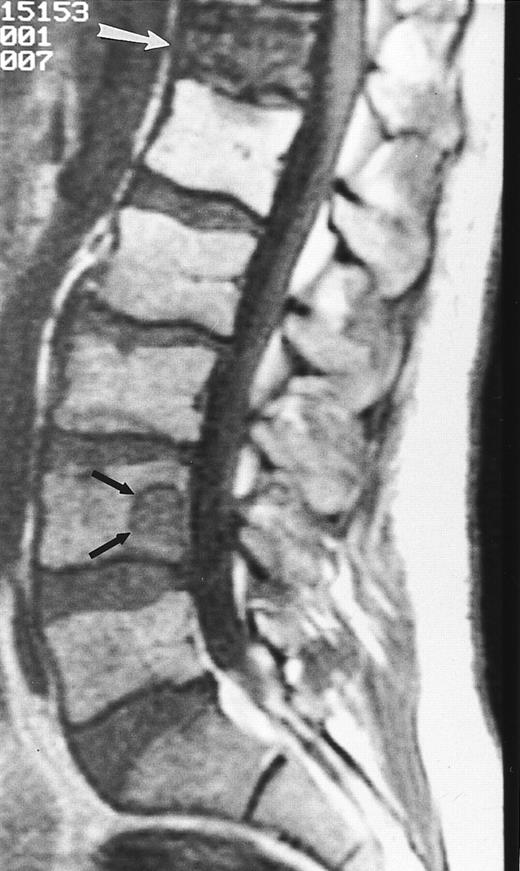

A 38-year-old man with solitary bone plasmacytoma and unsuspected lesions on MR images. Sagittal T1-weighted (600/20, TR/TE) MR image of the spine shows primary tumor in T12 (arrow) and additional focus of disease in L4 (short arrows). Conventional radiographs and CT scans failed to show the lesion in L2. Note characteristic postradiation bright signal in L1.